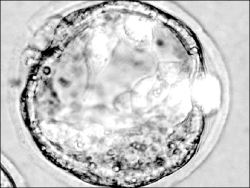

Madrid, 31 de octubre. Críticas de la Iglesia

católica y aplausos de la comunidad científica acogieron

el decreto del gobierno español que regula la investigación

con células madres embrionarias, que posibilitará la cura

de enfermedades como el Alzheimer, el Parkinson y la diabetes.